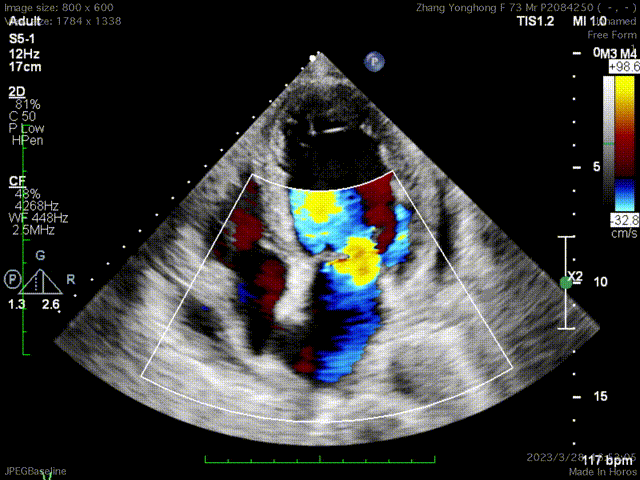

术前反流

手术采用左侧第六肋间微创切口心尖入路,在超声Mutlivue引导下清晰识别MitraFix®输送系统准确跨瓣,并将人工瓣膜准确释放于二尖瓣瓣环,瓣膜释放后支架贴合牢固,术后无瓣内反流及瓣周漏,二尖瓣前向血流通畅、跨瓣压差2mmHg,左心室流出道通畅,流出道血流速度0.8m/s,后顺利撤出输送系统,关闭心尖切口,手术顺利结束。

术后无反流